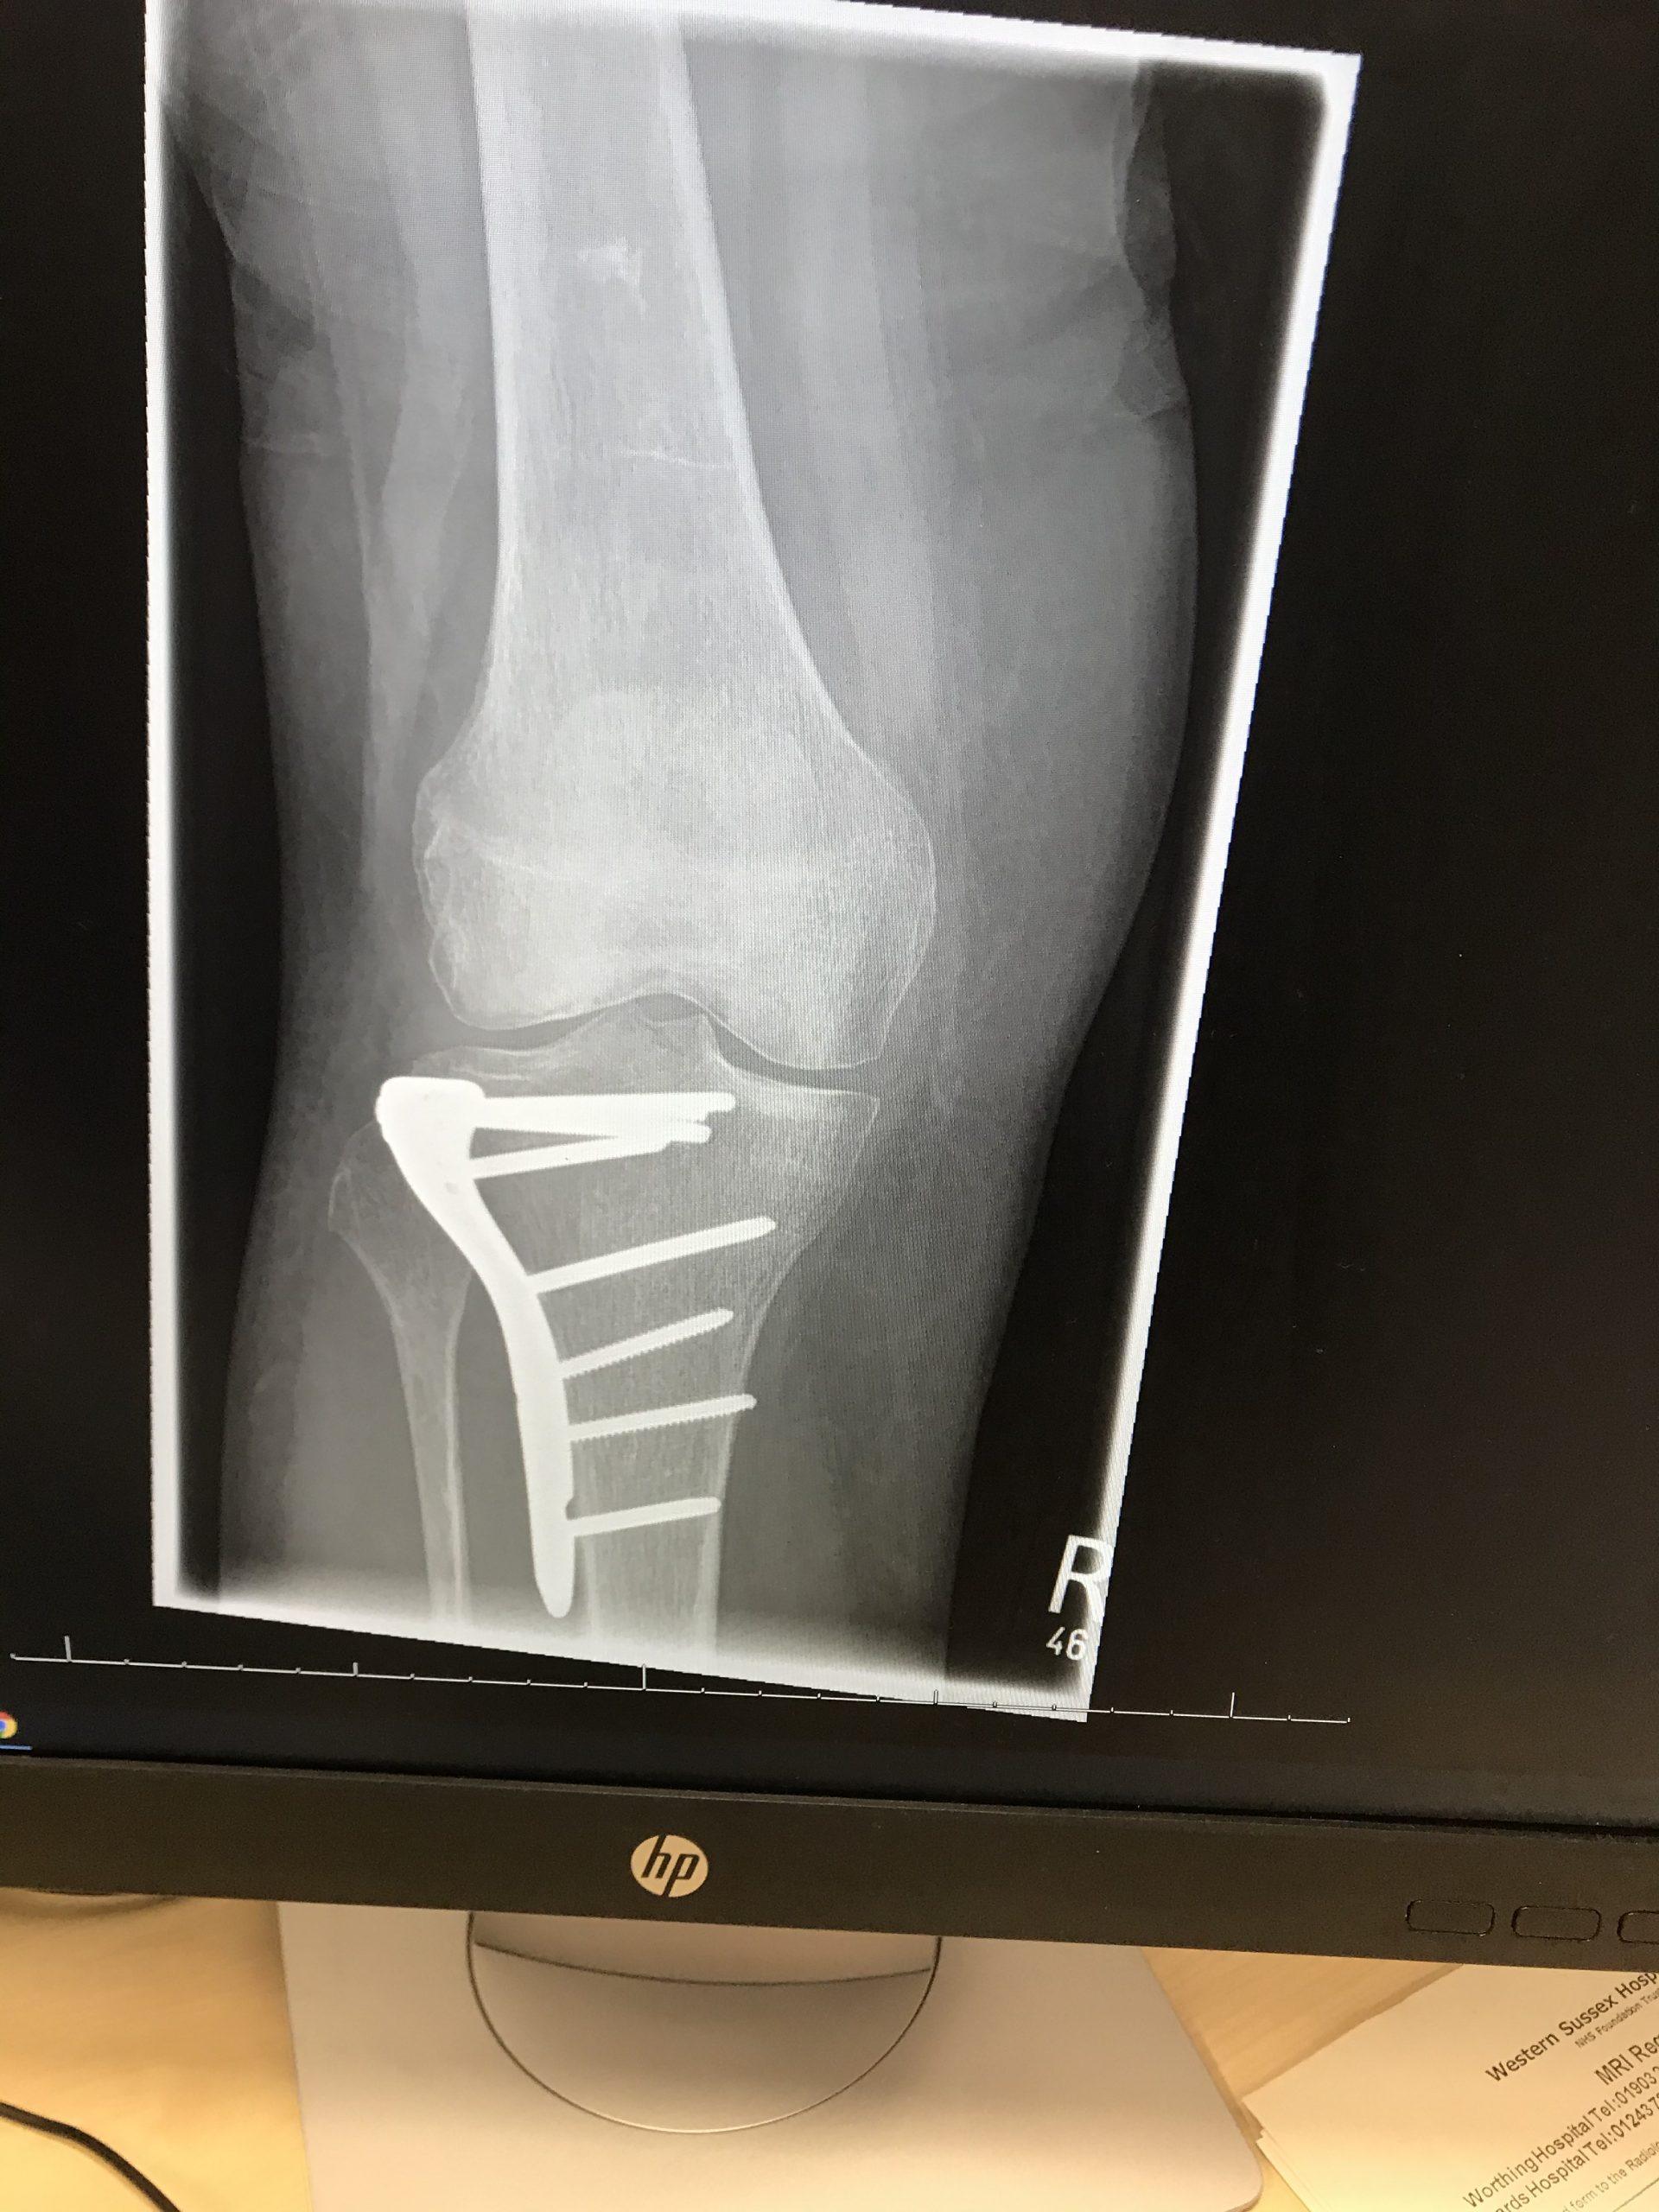

Our services are lead by Simon Palmer who is a Consultant Orthopaedic Surgeon with specialist training and experience in all aspects of knee surgery, including minimally invasive surgery and partial knee replacement.